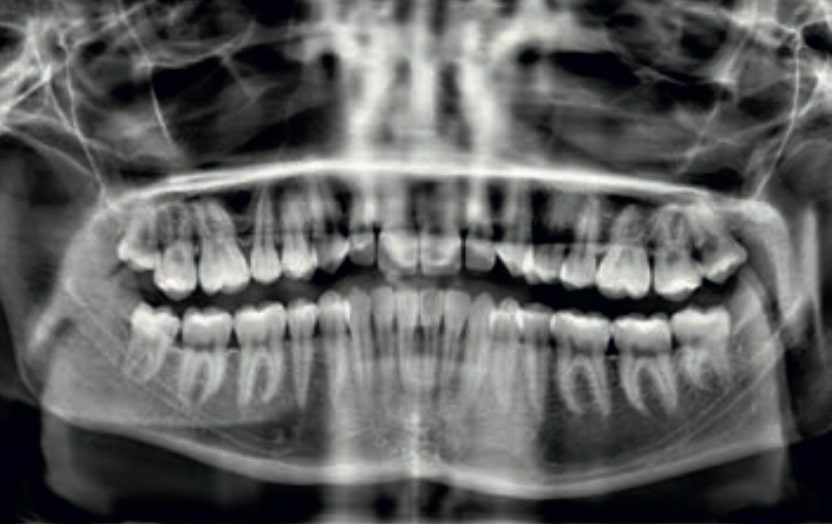

Chief complaint: The patient, a 19-year-old woman, was evaluated to undergo orthodontic treatment using the Angel Aligner Pro system. She presents with a skeletal Class III, mesofacial, with a dental Class III malocclusion and a 2 mm deviation of the lower midline to the left. Teeth 33 and 43 are out of the arch and cortical bone, with a crossbite issue on tooth 33. Fortunately, no functional issues affecting swallowing or breathing have been detected. The patient’s motivation for starting treatment was a general review of her dental and aesthetic health. The soft tissue analysis reveals mandibular protrusion that influences her facial profile. This diagnosis highlights the need for a comprehensive approach to address dental and skeletal misalignments, improving both the patient’s functionality and facial aesthetics.

- Patient Age: 19 years old

- Skeletal class III

- Dental Class III, 2 mm deviation of the lower midline to the left. 33 and 43 out of the arch and the cortical bone.

- Crossbite of 33.

- Improve the root position of 33 and 43 in relationship with the cortical bone.

- Improve the Root Position of Teeth 33 and 43: Optimize the position of the roots of teeth 33 and 43 in relation to the cortical bone to ensure adequate bone support and long-term stability.